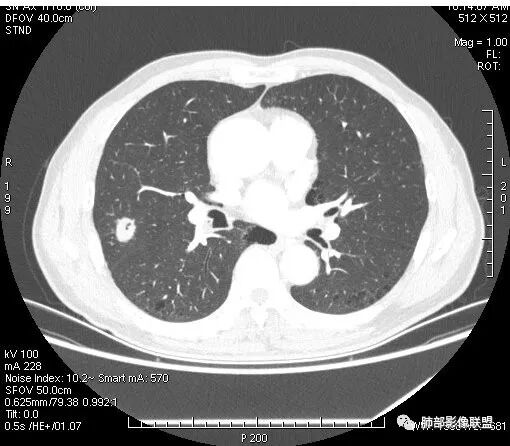

患者右上肺占位,内部强化不均,有空泡,有血管穿过,血管聚集现象,似有胸膜牵拉,考虑恶性

右肺上叶后段占位病灶,病灶不规则,周围胸膜线性牵拉,病灶部分周围有晕,病灶内见不规则空洞,未见明显引流支气管,长毛刺,多分叶、肿块边缘部分L型,可见血管直接供养。增强见点状坏死、病灶内血管。综上考虑恶性可能性大,鉴别隐球菌。

右肺上叶结节,浅分叶膨隆,边缘可见胸膜牵拉及血管集束,不规则厚壁空洞,不均匀强化,血管进入病灶,边缘毛燥,考虑低分化腺癌,鉴别隐球菌。

晨读:双肺胸膜下多发小气囊,大小不一,右肺结节,内部可见小空洞,洞壁光滑,厚薄不一,偏心性生长,近段血管束增粗,有分叶,毛刺(软),有晕征,平扫密度尚可,增强后不均匀强化,可见低密度坏死,及部分血管穿行,体检发现,考虑恶性:腺癌,鉴别炎性结节

右上叶结节,轻分叶,结节有长短不一毛刺,结节周围GGO边界清,有血管集束征,肺窗结节周围似可见卫星灶,可见鬼脸征,良恶性征象都有,但GGO边界清,浸润性腺癌耍考虑,临床症状轻微,体捡发现,似可见卫星灶和鬼脸征,炎性肉芽肿TB或隐球菌要鉴别。

右肺上叶结节,周围毛刺明显,其内有小炮征,分叶,强化中度,其内可见坏死,支气管有截断,考虑腺癌,鳞癌待排。病灶的上缘有一个小支气管进入,然后截断了

晨读:男,67岁,体检发现右肺结节。近圆形,支气管及伴行血管进入结节,进入结节后支气管堵塞,血管走形尚自然,结节内血管边缘凹凸不平。远端边缘见毛刺(软毛刺?)及分叶。见胸膜牵拉。实变中见空洞。整体膨胀感不明显。考虑炎性肉芽肿可能,隐球菌病可能性大。注意鉴别鳞癌、结核。

1.右肺上叶后段类圆形结节影,密度不均,有坏死空洞,坏死比较彻底,内外壁都较清楚。

2.病灶有浅切迹,没有深分叶,毛刺大多细长且柔软。

3.可见棘状突起及胸膜牵拉,但未见胸膜凹陷。

4.病灶轻到中度强化。病灶内血管走行较完好,病灶旁血管局部显示粗大。

6.灶周见小结节影(卫星灶),边界不甚清晰。